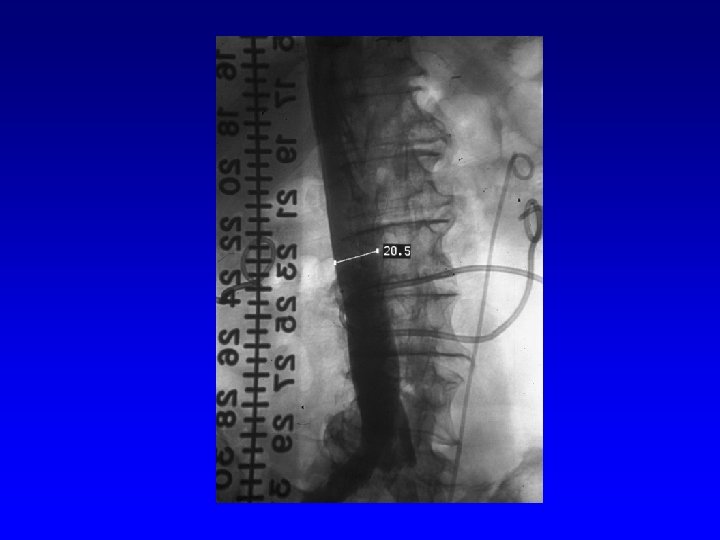

IVC Filter Removal Straight forward and Complex

Removal of an “Intravascular Foreign Body” Straight forward Loop snare Grasping device Complex Multiple devices used including angioplasty balloons, bronchoscopy forceps, and the“in situ” snare technique.